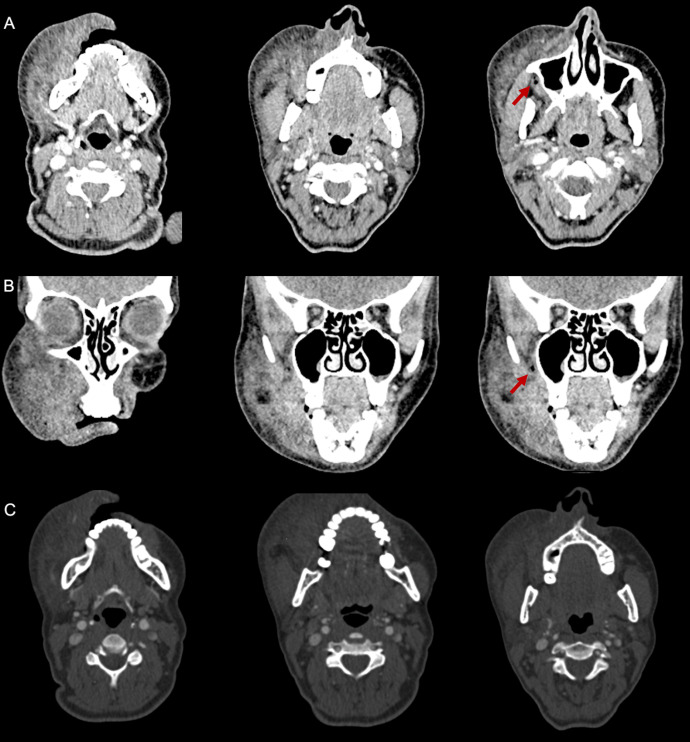

This case report highlights a rare complication of root canal treatment involving the inadvertent extrusion of sodium hypochlorite solution, resulting in a sodium hypochlorite-induced facial hematoma. A 44-year-old female patient presented significant right hemifacial swelling and ecchymosis following root canal therapy. Computed tomography imaging confirmed a hematoma involving the facial region without active signs of bleeding. Sodium hypochlorite, a potent cytotoxic agent commonly used in root canal procedures, was identified as the causative agent. Treatment consisted of prednisone, antibiotics, and NSAIDs, resulting in gradual improvement over a month. The cytotoxic properties of sodium hypochlorite, its variable concentrations, and risk factors associated with facial hematomas are discussed. It is essential to emphasize the rarity of such hematomas and highlight the need for precise technique, vigilant monitoring, and interdisciplinary collaboration to mitigate risks and prioritize patient safety.